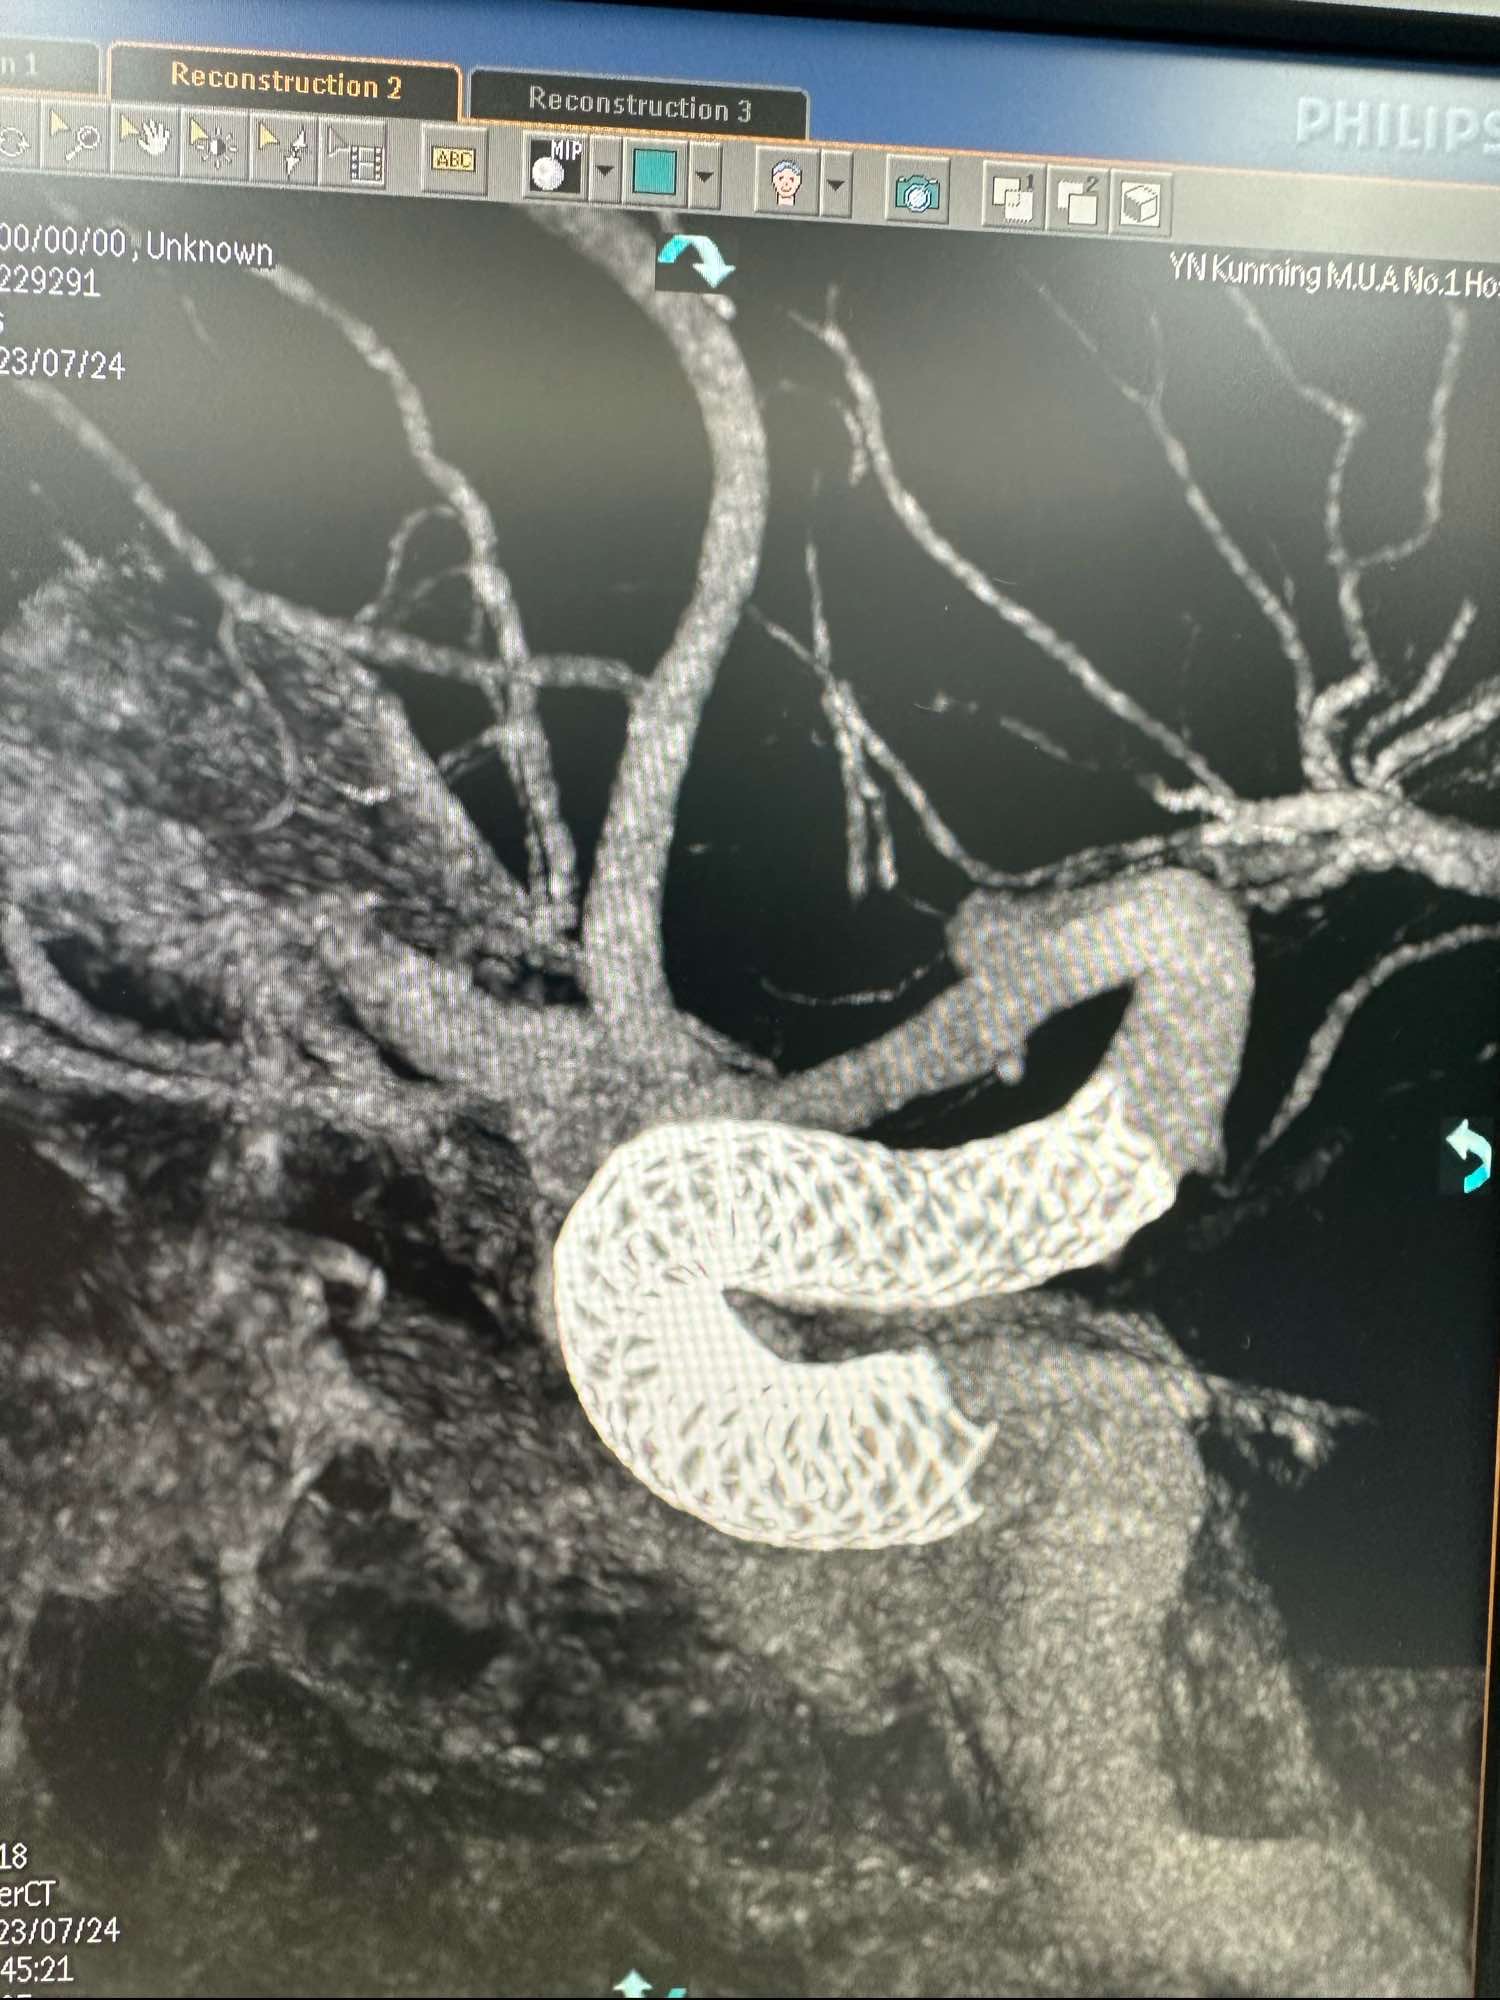

王LY,女,71岁,左侧眼动脉段动脉瘤,给予Lattice密网支架植入

术前的3D

另外一个角度

根据载瘤动脉的直径,选取4.4*20的Lattice的密网支架.进行原位释放.

支架在床突端打开不良,考虑血管扭曲,不停的进行支架摆动,最终打开

进行支架重建

另外一个角度见支架打开可